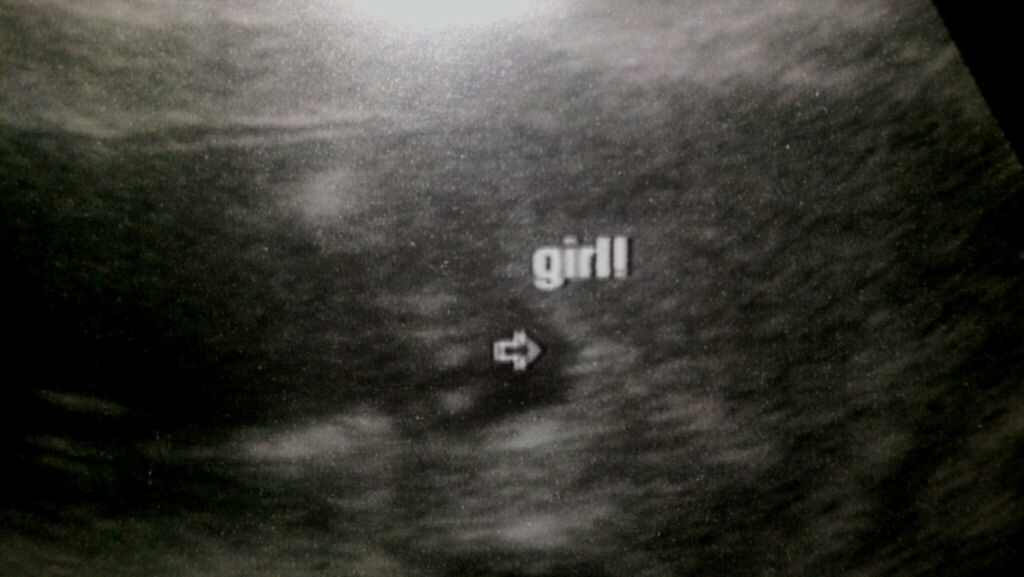

after 3 boys I finally get my girl, had my ultrasound and the tech said 99.9 % GIRL!!! Still in shock but over the moon!!! Thanks everyone for guessing girl, you were all right!Attachment 7397